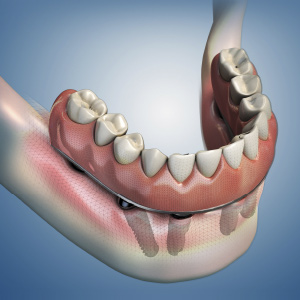

Dental Rehabilitation of the Atrophic Maxilla

This Compendium eBook features a continuing education (CE) article presents important diagnostic and treatment planning principles of the All-on-4 treatment concept for the rehabilitation of the atrophic maxillary arch, and includes a case report illustrating free-hand implant placement using this treatment approach.

Implantology Solutions

This Compendium eBook offers a continuing education (CE) article that examines treatment planning for full-arch reconstruction with implant overdentures. A long-term case report is also featured in this eBook, highlighting the steps involved in a full-arch reconstruction using transitional ...

Planning Full-Arch Reconstructions for Today and Tomorrow: Implant Overdentures and Fixed Restorations

This Compendium eBook features a continuing education (CE) article that discusses strategic implant treatment planning that takes into consideration the future restoration treatment needs of patients. Download to earn 2 FREE CEU now!